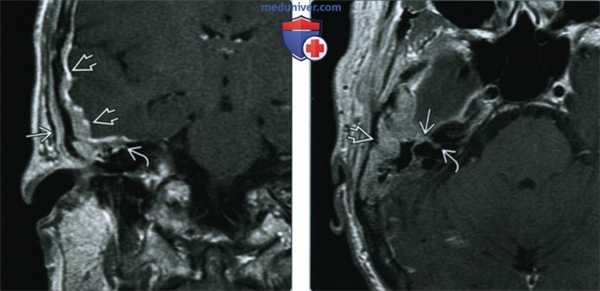

(Слева) При МРТ Т1 с КУ в корональной проекции у пациентки 60 лет, страдающей раком молочной железы и парезом правого лицевого нерва, вдоль чешуи височной кости и каменистого гребня определяется контрастный метастаз в твердой мозговой оболочке с ровными контурами. Опухоль достигает коленчатого ганглия. Обратите внимание на экстракраниальную опухоль с латеральной стороны пораженной чешуи височной кости.

(Справа) При МРТ Т1 с КУ в аксиальной проекции определяется опухоль твердой мозговой оболочки, инфильтрирующая каменистый гребень, распространяющаяся периневрально и достигающая коленчатого ганглия ЧН VII и дна внутреннего слухового прохода.